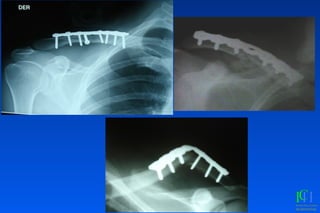

Fx Clavícula

Fx Clavicula: Criterios quirúrgicos

✓Fx abiertas

✓Hombro flotante

✓Pseudoartrosis

✓Interposicion de partes blandas

✓Compromiso neurovascular

✓Compromiso pleuropulmonar